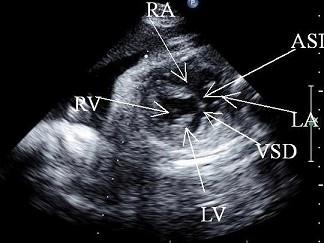

问题 胎儿心脏超声检查如图,最可能的诊断是?(?)

选项 A.法四 B.右心发育不良综合征 C.左心发育不良综合征 D.心内膜垫缺损 E.大动脉换位(TGA)

答案 D